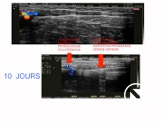

A 10 jours , le processus est déjà visible . A 3 mois , il persiste un cordon fibreux qui va disparaitre en 1 an environ .